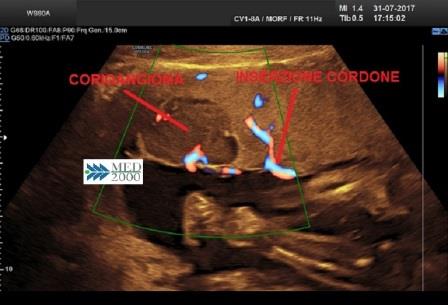

All'esame ecografico il corioangioma si presenta come una massa rotondeggiante, ben delimitata, ipoecogena o mista, di diametro variabile da 1 a 5 cm.

E' in genere localizzato vicino alla inserzione del cordone ombelicale sulla superficie fetale della placenta, spesso può sporgere in cavità amniotica.

Altra caratteristica evidenziabile al Color-Doppler è un evidente flusso ematico e/o un grande vaso nutritivo afferente.